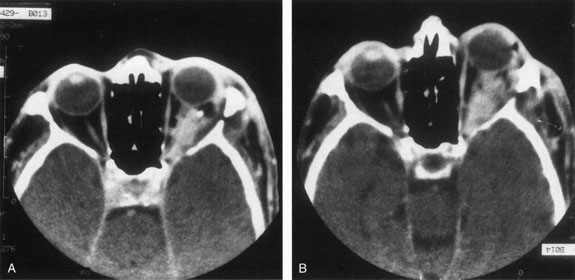

Fig. 14. Orbital venous flow malformation. Axial computed tomography scan showing an ill-defined, dense, inhomogeneous orbital lesion with the patient in a supine position (A). Note the phlebolith, which indicates venous stagnation. As the venous flow malformation distends with the patient in the prone position, the lesion enlarges (B). (Courtesy of Dr. John V. Linberg, University of West Virginia, Morgantown, WV)